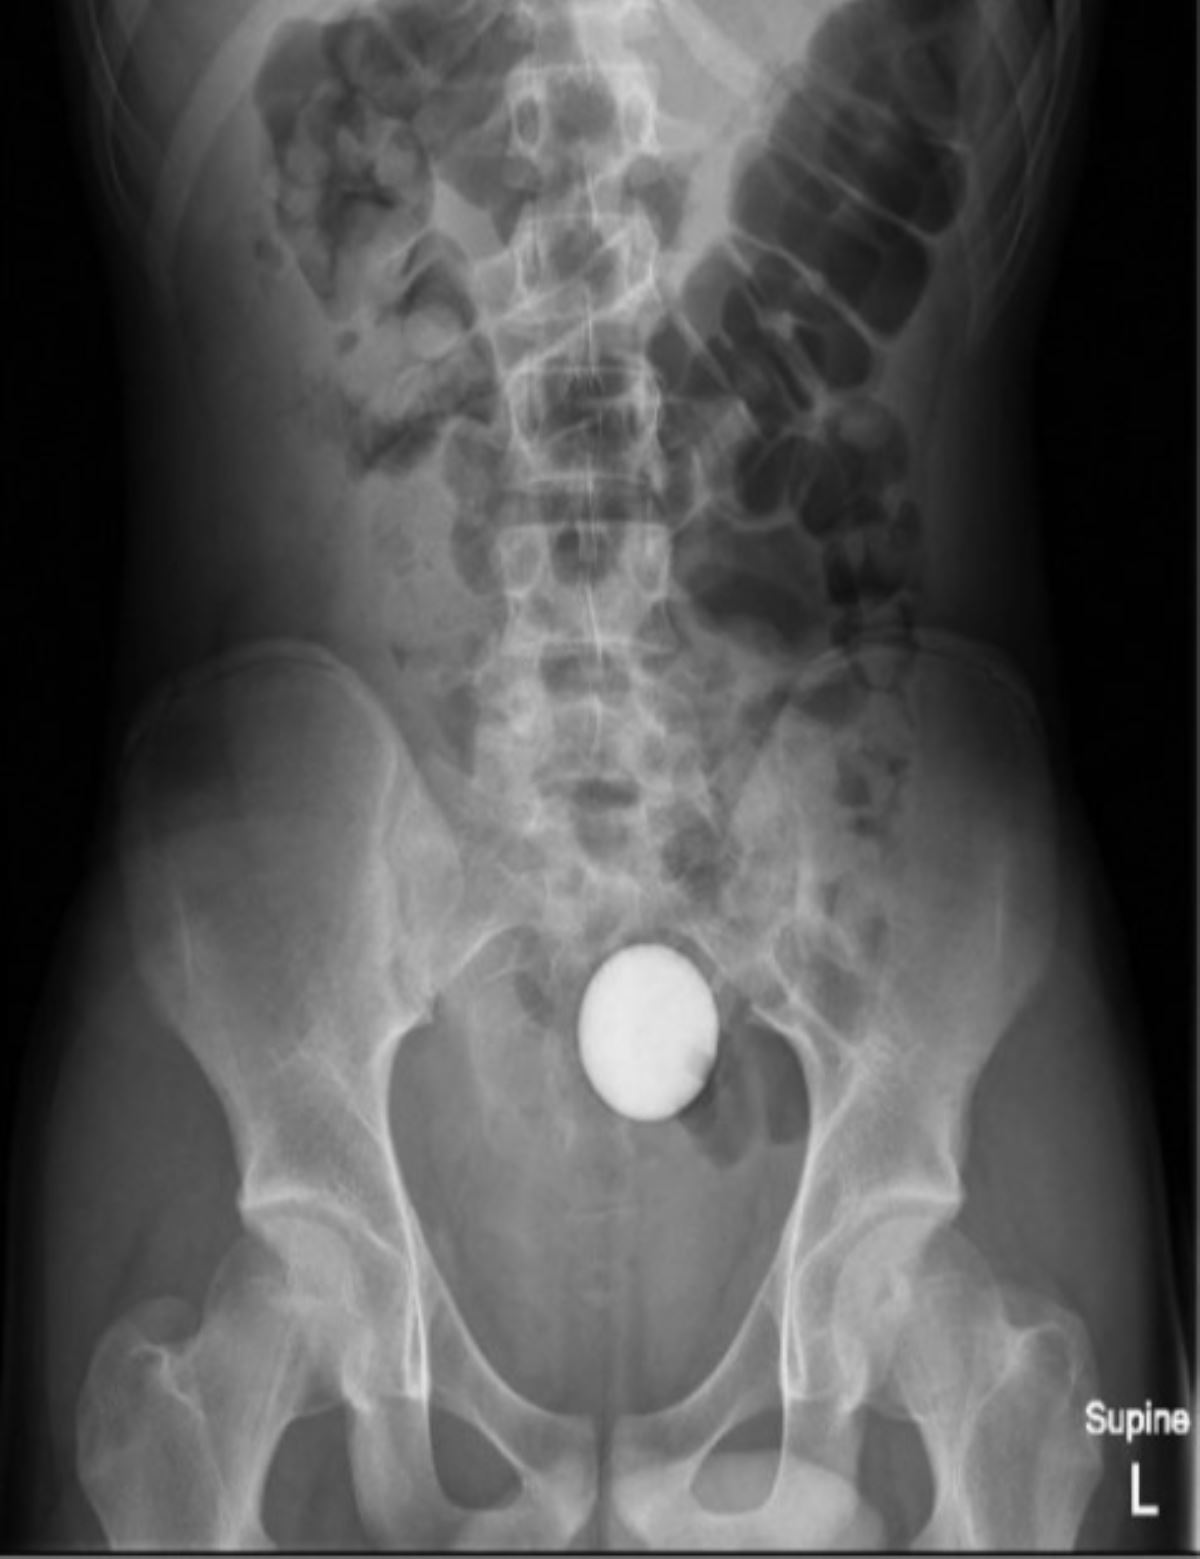

Acil serviste çekilen röntgende, topun kalın bağırsağın son kısmı olan sigmoid kolonuna yerleştiği görüldü.